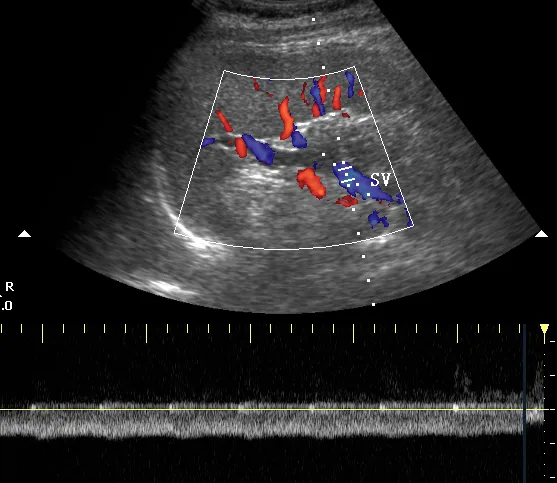

彩色多普勒,正常脾脏,显示脾门处红色的脾动脉(SA)和蓝色的脾静脉(SV) 。

脉冲多普勒,正常脾脏,显示脾动脉搏动性血流曲线(图1,SA)和脾静脉连续性血流曲线(图2,SV)。